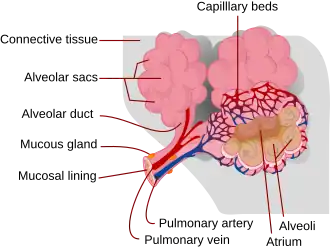

Connective tissue

The connective tissue of the lungs is made up of elastic and collagen fibres that are interspersed between the capillaries and the alveolar walls. Elastin is the key protein of the extracellular matrix and is the main component of the elastic fibres.[19] Elastin gives the necessary elasticity and resilience required for the persistent stretching involved in breathing, known as lung compliance. It is also responsible for the elastic recoil needed. Elastin is more concentrated in areas of high stress such as the openings of the alveoli, and alveolar junctions.[19] The connective tissue links all the alveoli to form the lung parenchyma which has a sponge-like appearance. The alveoli have interconnecting air passages in their walls known as the pores of Kohn.[20]

Respiratory zone

The conducting zone of the respiratory tract ends at the terminal bronchioles when they branch into the respiratory bronchioles. This marks the beginning of the terminal respiratory unit called the acinus which includes the respiratory bronchioles, the alveolar ducts, alveolar sacs, and alveoli.[27] An acinus measures up to 10 mm in diameter.[28] A primary pulmonary lobule is the part of the lung distal to the respiratory bronchiole.[29] Thus, it includes the alveolar ducts, sacs, and alveoli but not the respiratory bronchioles.[30]

The unit described as the secondary pulmonary lobule is the lobule most referred to as the pulmonary lobule or respiratory lobule.[25]: 489 [31] This lobule is a discrete unit that is the smallest component of the lung that can be seen without aid.[29] The secondary pulmonary lobule is likely to be made up of between 30 and 50 primary lobules.[30] The lobule is supplied by a terminal bronchiole that branches into respiratory bronchioles. The respiratory bronchioles supply the alveoli in each acinus and is accompanied by a pulmonary artery branch. Each lobule is enclosed by an interlobular septum. Each acinus is incompletely separated by an intralobular septum.[28]

The respiratory bronchiole gives rise to the alveolar ducts that lead to the alveolar sacs, which contain two or more alveoli.[20] The walls of the alveoli are extremely thin allowing a fast rate of diffusion. The alveoli have interconnecting small air passages in their walls known as the pores of Kohn.[20]

Alveoli

Alveoli consist of two types of alveolar cell and an alveolar macrophage. The two types of cell are known as type I and type II cells[32] (also known as pneumocytes).[3] Types I and II make up the walls and alveolar septa. Type I cells provide 95% of the surface area of each alveoli and are flat ("squamous"), and Type II cells generally cluster in the corners of the alveoli and have a cuboidal shape.[33] Despite this, cells occur in a roughly equal ratio of 1:1 or 6:4.[32][33]

Type I are squamous epithelial cells that make up the alveolar wall structure. They have extremely thin walls that enable an easy gas exchange.[32] These type I cells also make up the alveolar septa which separate each alveolus. The septa consist of an epithelial lining and associated basement membranes.[33] Type I cells are not able to divide, and consequently rely on differentiation from Type II cells.[33]

Type II are larger and they line the alveoli and produce and secrete epithelial lining fluid, and lung surfactant.[34][32] Type II cells are able to divide and differentiate to Type I cells.[33]

The alveolar macrophages have an important role in the immune system. They remove substances which deposit in the alveoli including loose red blood cells that have been forced out from blood vessels.[33]

Blood supply

The lungs have a dual blood supply provided by a bronchial and a pulmonary circulation.[4] The bronchial circulation supplies oxygenated blood to the airways of the lungs, through the bronchial arteries that leave the aorta. There are usually three arteries, two to the left lung and one to the right, and they branch alongside the bronchi and bronchioles.[32] The pulmonary circulation carries deoxygenated blood from the heart to the lungs and returns the oxygenated blood to the heart to supply the rest of the body.[32]

The major function of the lungs is gas exchange between the lungs and the blood.[67] The alveolar and pulmonary capillary gases equilibrate across the thin blood–air barrier.[34][68][69] This thin membrane (about 0.5 –2 μm thick) is folded into about 300 million alveoli, providing an extremely large surface area (estimates varying between 70 and 145 m2) for gas exchange to occur.[68][70]